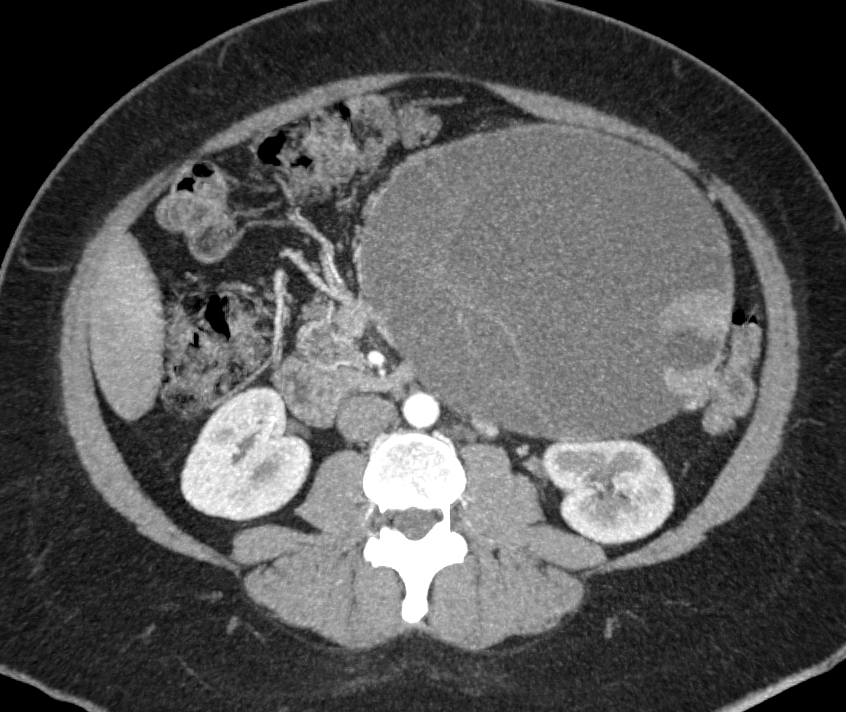

9) In this patient with small bowel GI bleed the best dx is?

angiodysplasia

GIST tumor

small bowel adenocarcinoma

metastatic melanoma